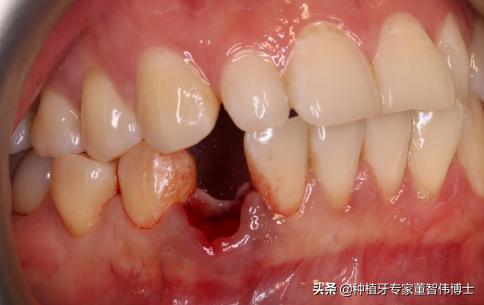

1、 43牙拔除后即刻种植+GBR